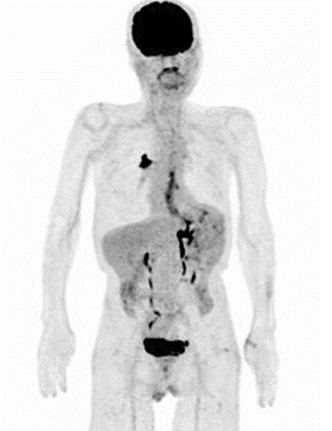

PET 右肺癌